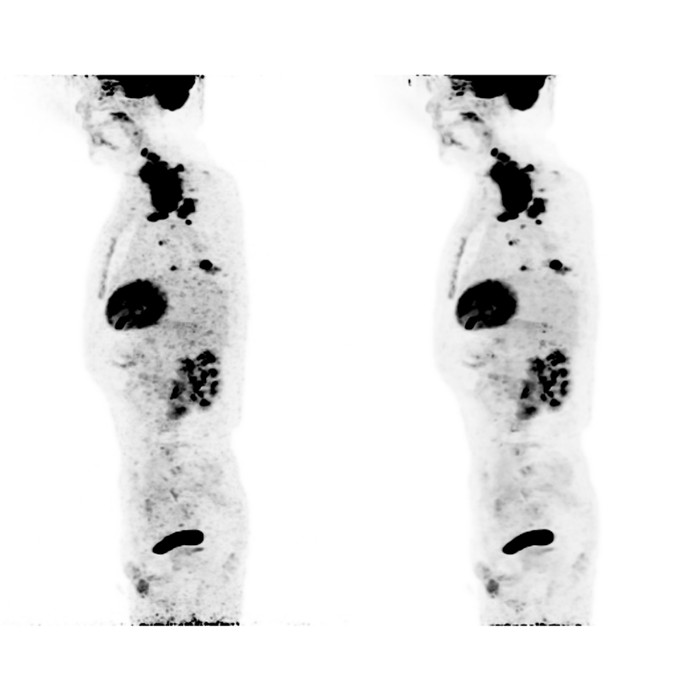

▲左:50%低劑量圖像,右:新型AI重建圖像

上圖中,新型AI重建圖像的噪聲水平大大低于傳統(tǒng)低劑量重建結(jié)果(約為原來(lái)的50%),圖像信噪比顯著提升。